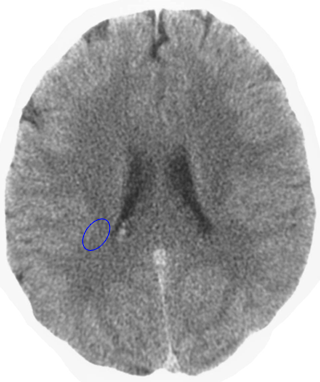

Which is the brain relais that is shown here? 25 Questions each cycle, try more!

Question 1 of 25

Middle ear mucosa left

Rectal mucosa

Coronary arteries, aortic arch, carotid arteries, bradycardia, penile sensitivity, clitoral sensitivity

Liver

Left hemispheres of the retinas

Lesser curvature of the stomach, mucosa of the bile ducts, pancreatic ducts, bulb of the duodenum